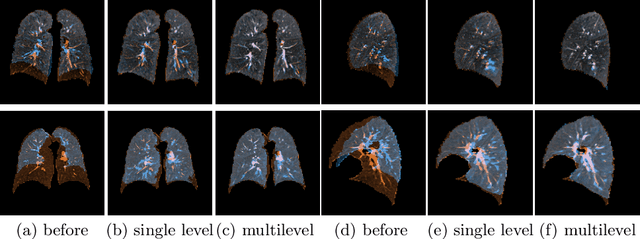

Abstract:Deep-learning-based registration methods emerged as a fast alternative to conventional registration methods. However, these methods often still cannot achieve the same performance as conventional registration methods, because they are either limited to small deformation or they fail to handle a superposition of large and small deformations without producing implausible deformation fields with foldings inside. In this paper, we identify important strategies of conventional registration methods for lung registration and successfully developed the deep-learning counterpart. We employ a Gaussian-pyramid-based multilevel framework that can solve the image registration optimization in a coarse-to-fine fashion. Furthermore, we prevent foldings of the deformation field and restrict the determinant of the Jacobian to physiologically meaningful values by combining a volume change penalty with a curvature regularizer in the loss function. Keypoint correspondences are integrated to focus on the alignment of smaller structures. We perform an extensive evaluation to assess the accuracy, the robustness, the plausibility of the estimated deformation fields, and the transferability of our registration approach. We show that it archives state-of-the-art results on the COPDGene dataset compared to the challenge winning conventional registration method with much shorter execution time.

Abstract:We present a novel multilevel approach for deep learning based image registration. Recently published deep learning based registration methods have shown promising results for a wide range of tasks. However, these algorithms are still limited to relatively small deformations. Our method addresses this shortcoming by introducing a multilevel framework, which computes deformation fields on different scales, similar to conventional methods. Thereby, a coarse-level alignment is obtained first, which is subsequently improved on finer levels. We demonstrate our method on the complex task of inhale-to-exhale lung registration. We show that the use of a deep learning multilevel approach leads to significantly better registration results.